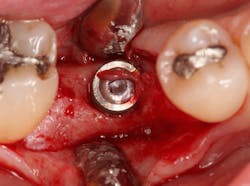

Excellent interseptal bone width was present, both buccal and lingual plates were present, and an adequate amount of bone was present coronal to the inferior alveolar nerve to allow for immediate implant placement. A sulcular incision was made around K and the adjacent teeth, and a full-thickness buccal and lingual flap was reflected. The tooth was sectioned in half, and the mesial and distal roots were elevated. The socket was degranulated with a round diamond bur and copiously irrigated with chlorhexidine gluconate 0.12% rinse. An osteotomy was completed in the interseptal area, and a bone-level 4.8- x 10-mm implant was placed to 35 Ncm. A mixture of cancellous and cortical allograft was infused with autogenous plasma-rich growth factor (PRGF), which was isolated during a preprocedural blood draw. The mixture was packed into the residual socket, slightly coronal to the implant platform to account for predictable resorption during healing. (13)

A 15- x 20-mm Ossix Plus membrane was hydrated in sterile saline for three minutes and trimmed to extend roughly 3 mm beyond the buccal and lingual extent of the bone graft and roughly 1 mm from the adjacent teeth. A sterile template is included in each membrane package; it can be trimmed to the appropriate dimensions and superimposed on the Ossix Plus membrane for final trimming to ensure the exact dimensions desired are obtained. This membrane can also be sutured, if necessary. When this technique is used, it is important to pass the suture needle through the membrane at a 90-degree angle to avoid tearing the membrane.

At this point, releasing incisions (vertical incisions and/or periosteal releasing incisions) can be made to achieve primary closure or to leave the membrane exposed and let the area heal by secondary intention. With the Ossix Plus membrane’s increased resistance to bacterial collagenase and the stresses of the oral environment, I feel comfortable leaving the membrane exposed and allowing the attached gingiva to heal over the membrane. This will result in reduced swelling and discomfort during healing, and there is less risk of damaging the mental nerve as it exits the mental foramen and fans laterally into the tissue. Attached gingiva around an implant will facilitate a more accurate impression, easier delivery of the restoration (and increased resistance to cement penetrating subgingivally), and easier hygiene for the patient. Also, when the implant is uncovered after healing, a tissue punch can be used, and there will generally be no need for a flap and sutures, thus improving the patient experience. Conversely, primary closure is imperative when performing a lateral or vertical ridge augmentation with or without simultaneous implant placement. Generally, when the extraction socket walls are intact, leaving the membrane exposed and allowing attached gingiva to grow over the membrane is predictable.

In this case, I placed an autogenous fibrin clot, which was isolated from the fractionated blood draw, over the Ossix Plus membrane and sutured, without obtaining primary closure, using a CV-5 Gore-Tex (W.L. Gore & Associates Inc.). This technique is designed to help facilitate the formation of a blood clot over the Ossix Plus membrane. It can be used with the addition of a collagen plug over the membrane, or you can just suture and allow a natural clot to form.